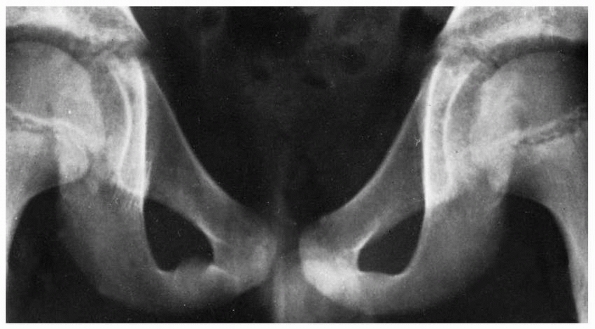

![]() |

FIGURE 20-22 A. An example of an anterior posterior pelvic radiograph where the sacral fracture is not well visualized. B. CT scan of the patient showing the sacral fracture.

In one study comparing radiographs with CT scans in a consecutive

pelvic CT scans, only three sacral fractures were identified with plain

radiographs whereas nine sacral fractures were identified with CT (Fig. 20-22).30